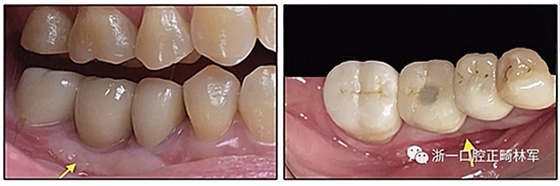

圖10.經(jīng)過7個月后,以每月1毫米的速度牽引下頜左側(cè)第二前磨牙,正畸產(chǎn)生的種植部位長約7毫米。通過使用固定矯治器保持間隙6個月。根尖X線片顯示第二前磨僅有少量牙根遠(yuǎn)中面吸收。

圖12.將種植體植入正畸產(chǎn)生的間隙中的步驟:A,將下頜左側(cè)第二前磨牙向遠(yuǎn)中移動以在前磨牙之間產(chǎn)生間隙; B,種植部位的咬合面觀; C,一個水平切口和兩個垂直切口,距相鄰牙齒1.5mm的距離; D,暴露的牙槽嵴的咬合面觀; E,測量牙槽嵴的寬度約6mm; F,手術(shù)導(dǎo)板顯示預(yù)備冠頸部的位置距離骨牙槽嵴頂僅1毫米; G,用球鉆修整牙槽嵴; H,建立3mm從手術(shù)導(dǎo)板的頸部輪廓到骨嵴的距離,以實(shí)現(xiàn)必要的生物學(xué)寬度; I,引導(dǎo)針顯示了截骨的角度; J,3.5×10mm種植體完全置于骨內(nèi); K,一個覆蓋螺帽就位; 和L,縫合。

成人正畸患者通常有缺牙和牙槽骨萎縮。假設(shè)相鄰的牙齒是牙周健康的,可以通過正畸牙齒移動擴(kuò)大狹窄的牙脊。該過程是通過牙周膜牽引以產(chǎn)生束骨:骨內(nèi)礦化的膠原束(Sharpey's纖維)。當(dāng)牙根表面與萎縮牙槽骨的致密骨皮質(zhì)接觸時,牙根側(cè)面吸收是常見的。使用輕力使下頜前磨牙的平移可減少牙周膜壞死和牙根側(cè)面吸收,但這也大大提高了牙齒移動的速度。當(dāng)牙齒之間的間隙被打開形成種植位置時,新形成的牙槽嵴主要是未成熟的束骨,并且一旦形成就開始在高度和頰側(cè)寬度上萎縮。在種植體植入時建議牙槽嵴骨移植以補(bǔ)償預(yù)期的額外骨質(zhì)流失。強(qiáng)烈建議使用固定保持器進(jìn)行間隙保持,直到種植體支持式修復(fù)體的完成。盡管在種植體部位出現(xiàn)骨和軟組織問題,但獲得了極好的總體結(jié)果,差異指數(shù)DI(模型頭測評估)從28分降到了13分。